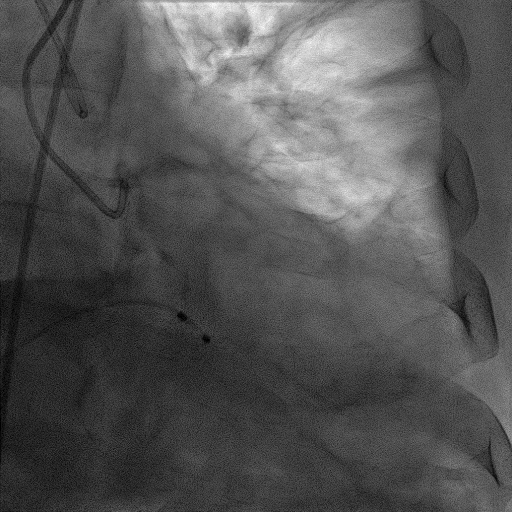

CAG:LAD近中段弥漫钙化,近段80%狭窄,中段90%狭窄,D190%狭窄,中间支近段90%狭窄,右冠近中段弥漫病变,最重狭窄50%。考虑患者胸痛症状可能为冠心病+AS共同作用,以及患者冠脉病变钙化严重,予以旋磨+PCI+TAVR一站式处理。

于中间支植入2.5*18mm支架

1.5mm旋磨头以16万RPM旋磨三次

3.0*15mm球囊后扩张

3.0*15mm球囊预处理LAD近段病变

复查冠脉造影结果满意

造影提示微少量返流,压力监测提示主动脉瓣压差7mmHg